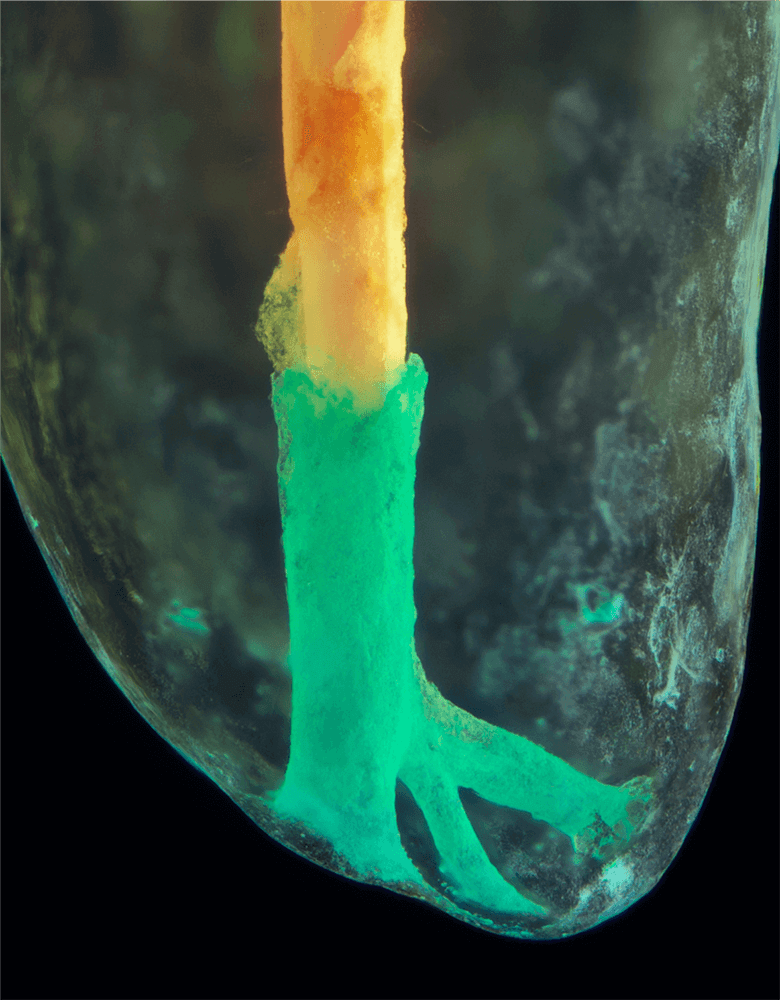

Das Verfahren, Zähne in durchsichtige Präparate zu überführen ist schon über 100 Jahre alt. Aber erst durch die Weiterentwicklung der alten Technik und die Kombination mit moderner Fotografie sowie der Entwicklung eines geeigneten Gefäßes zur Fotografie ist es meinem Vater Dr. Holm Reuver gelungen, einzigartige Bilder vom Inneren der Zähne aufzunehmen.

Die Bilder sind in verschiedenen Größen wählbar und auch als POPART-Variante erhältlich. Sie sind hervorragend geeignet für die Beratung von Patienten vor endodontischen Behandlungen, aber auch ein beliebter Eyecatcher im Wartezimmer. Außerdem haben die Bilder einen bedeutenden Stellenwert für die Erforschung der Pulpatopografie und für die Lehre im Bereich der Endodontie.

und die von ihm angefertigten Bilder, laden wir Sie ein, seine Begeisterung zwischen Wissenschaft und Kunst mit ihm zu teilen.